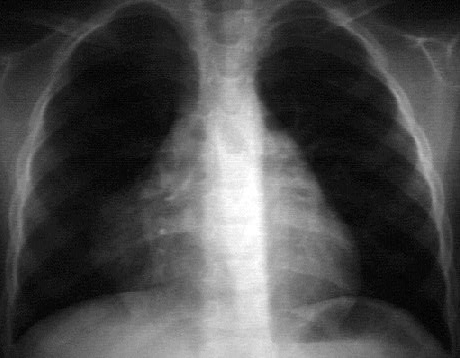

You are incorrect - the best interpretation of the chest X rays in this patient is pericardial calcification.

Your choice: Pericardial cyst

This chest X ray demonstrates a pericardial cyst. This PA view shows apparent prominence of the right heart border. Careful inspection shows a smooth, round, soft tissue density distinct from and adjacent to the right heart border. The typical appearance of a benign pericardial cyst.